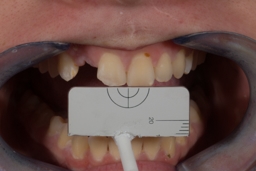

Minimal Prep Veneers to correct a discoloured tooth and improve form